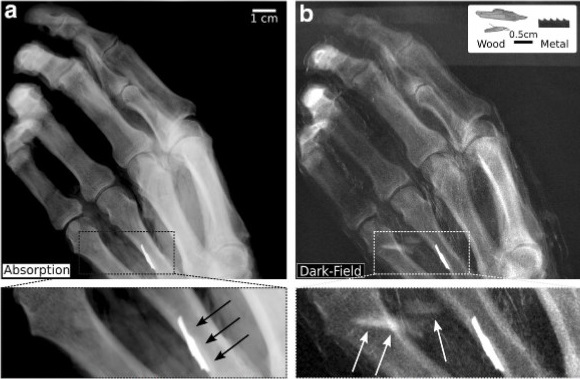

Since detection of retained wood is a frequent but challenging task in emergency care, this study aimed to demonstrate the improved foreign-body detection. By simulating a clinical setting, it was concluded that x-ray dark-field radiography enables the simultaneous detection of wooden and metallic particles in the extremities and that it has the potential to improve and simplify the current state-of-the-art foreign-body detection.

•    Grating-based x-ray dark-field imaging enables the detection of wood on plain radiography.

•    The signal-to-noise ratio of wood was six times higher compared to that obtained for conventional attenuation.

•    Conventional radiography image is acquired simultaneously with the dark-field image.